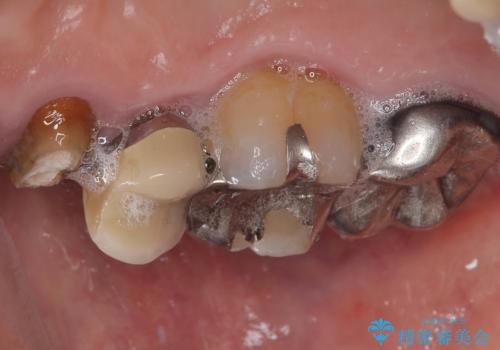

- 「以前治療した歯の被せものが外れてしまった」とのことで、右上の小臼歯の被せもの脱離を主訴に来院されました。

診察の結果、被せもの(クラウン)だけでなく、土台(コア)ごと外れてしまっている状態でした。根管治療済みの歯ではありますが、今回患者様のご希望により、根管治療の再治療は行わず、補綴処置のみを行う方針となりました。